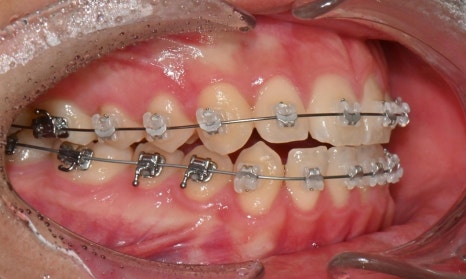

치료 시작 7개월 후 - 연세정원치과

치료 시작 7개월 후 사진으로, 치아 배열 후 아래 우측에 미니스크류를 식립하여 치아 중심선을 개선하는 중으로, 교합과 치아 중심선이 많이 개선된 것을 확인할 수 있습니다.

약 1년 간의 교정 치료를 통해 어긋나 있던 치아 중심선이 자연스럽게 맞춰졌고, 중심선 비대칭이 개선 및 하악 아랫입술 돌출도 눈에 띄게 호전되었습니다. 무엇보다 치료 기간 동안 앞니의 치근 흡수는 추가적인 진행 없이 안정적으로 유지되었습니다.

돌출을 조금 더 개선하는 것을 추천했으나, 환자가 갑자기 군 입대를 하게 되어 현 상태로 치료를 마무리하기로 하였습니다. 치료 전후 치아 위아래 중심선이 일치하며 좌우 어금니 교합도 향상되었습니다. 하악 치열의 후방 이동으로 아래 입술의 돌출도도 많이 개선되었습니다. 멀리서도 믿고 내원해주고, 치료 기간 동안 성실히 협조해준 환자분께 감사드리며 앞으로도 건강한 치아로 군 생활 잘 마치길 응원합니다 :)